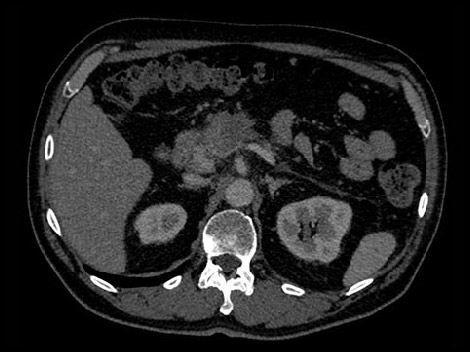

In this hypothetical example, the radiologists need more information about a visible mass in the pancreas in order make a confident diagnosis.

With a traditional CT, if the image is inconclusive, the patient may be asked to return for an additional scan.